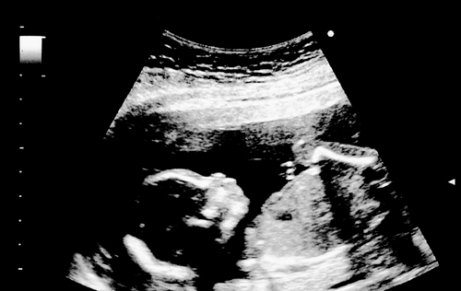

By the 18th week of pregnancy, the fetus measures around 5.5 inches and weighs approximately 6.5 or 7 ounces. The tiny baby’s movements are more and more vigorous.

During an ultrasound, you can observe the baby stretching and contracting his or her arms and legs. You may also see the fetus open and close its mouth as he or she learns to swallow.

Because of the transparency of the baby’s skin, his or her blood vessels are visible. Eyelashes and eyebrows also begin to appear and the child’s eyes and ears assume their permanent position. In an ultrasound, parents may get the chance to see their baby suck on his or her fingers.